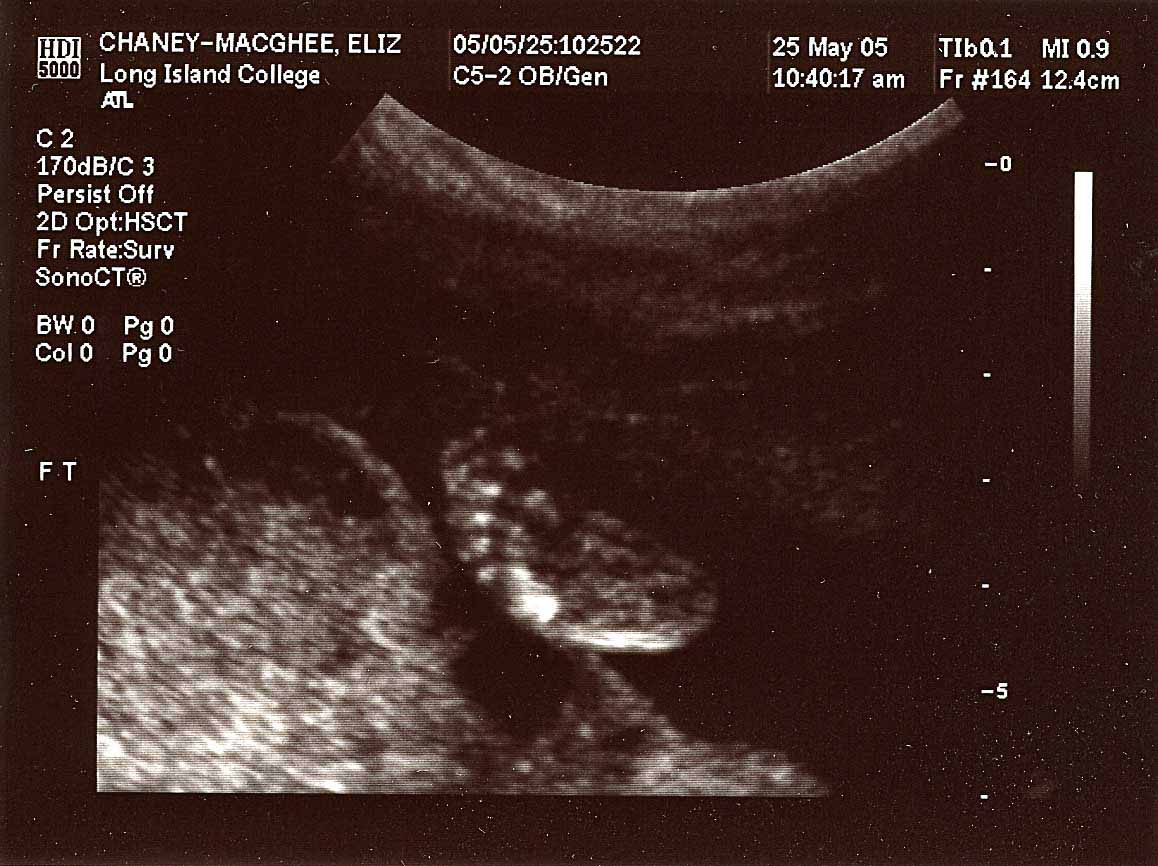

images taken 5/25/04, baby's weight estimated at 12 oz.

Close up, profile; 20 weeks.